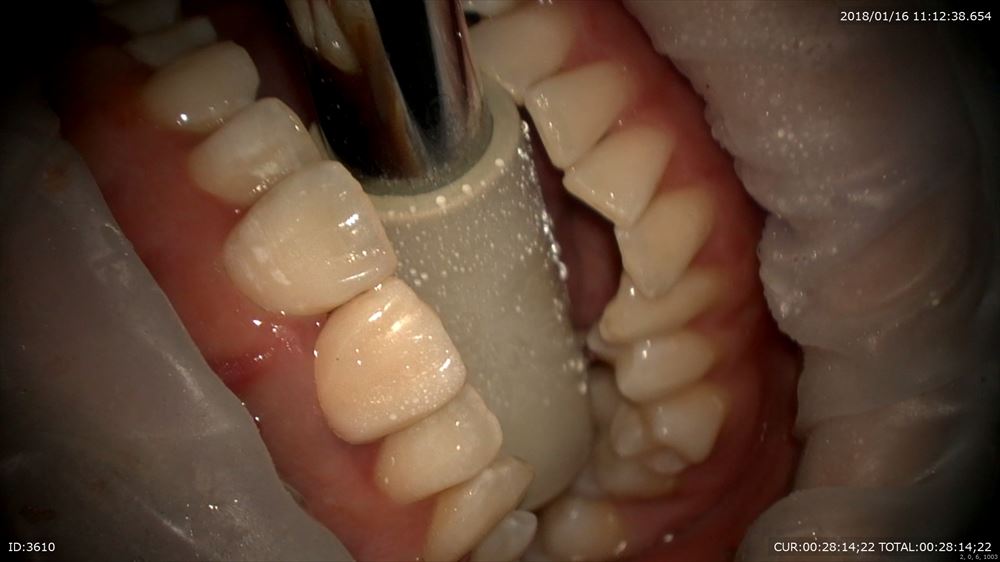

精密仮歯が重要。治療中も細菌感染を防ぐ為です。外していきます。

やっぱり銀歯虫歯。ここから最近感染がおきて根管が感染したと思われます。感染を染めて

丁寧に上部形成